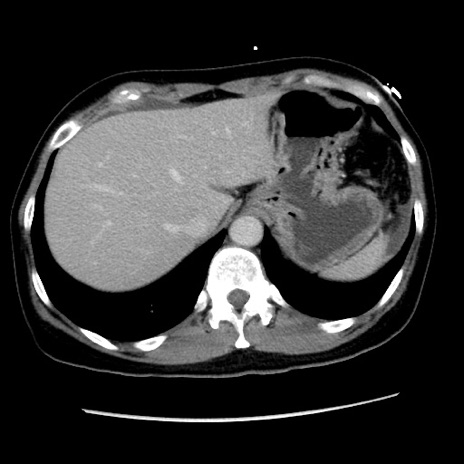

矢状断像

【症例】 50歳代女性

【主訴】 腹痛

【現病歴】前日生レバーを食べた。今朝に排便あり。 昼前に突然発症の腹痛を生じ、当院救急外来を受診した。

【身体所見】 意識清明、腹部:平坦、軟、下腹部やや左を中心に圧痛・反跳痛あり、筋性防御あり

【データ】WBC 7800、CRP 0.07